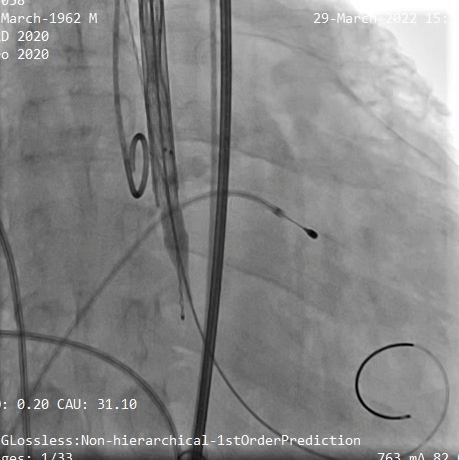

主动脉根部造影,主动脉瓣中度反流,采用23mm球囊预扩,有轻微腰征,无造影剂渗漏。

主动脉根部造影

球囊预扩